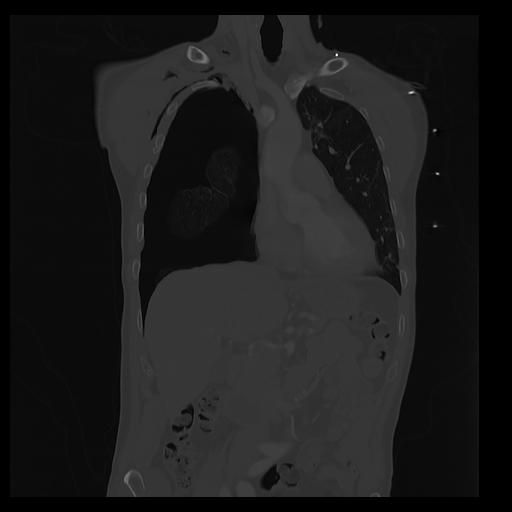

32 PULMON,CE,Coronal,3.000,PULMON,Coronal,